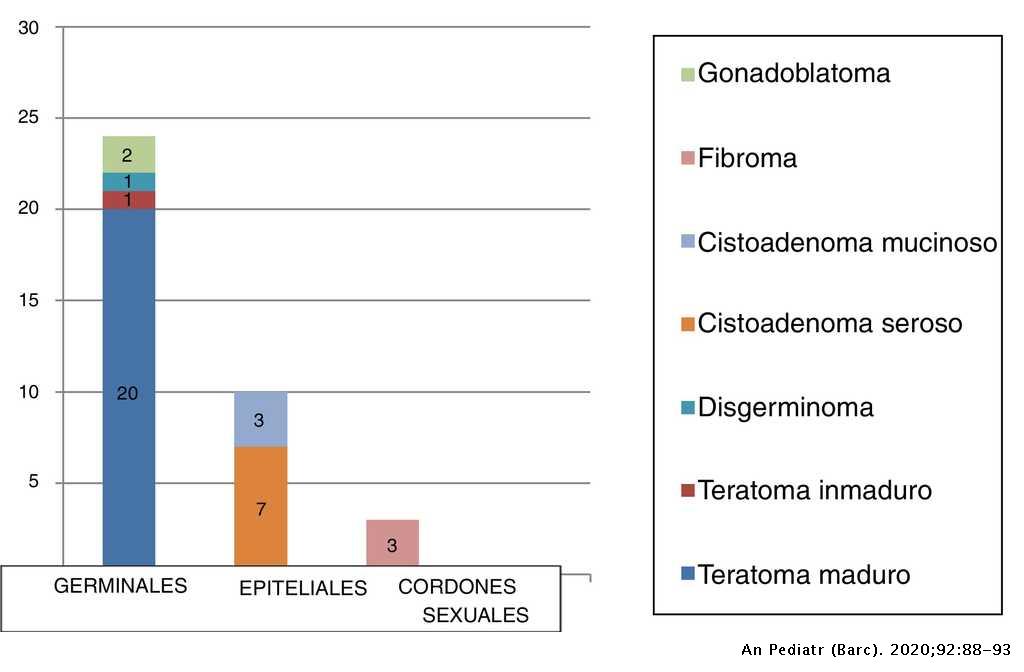

Productividad almohada puñetazo Análisis de los tumores sólidos ováricos pediátricos en nuestra población | Anales de Pediatría